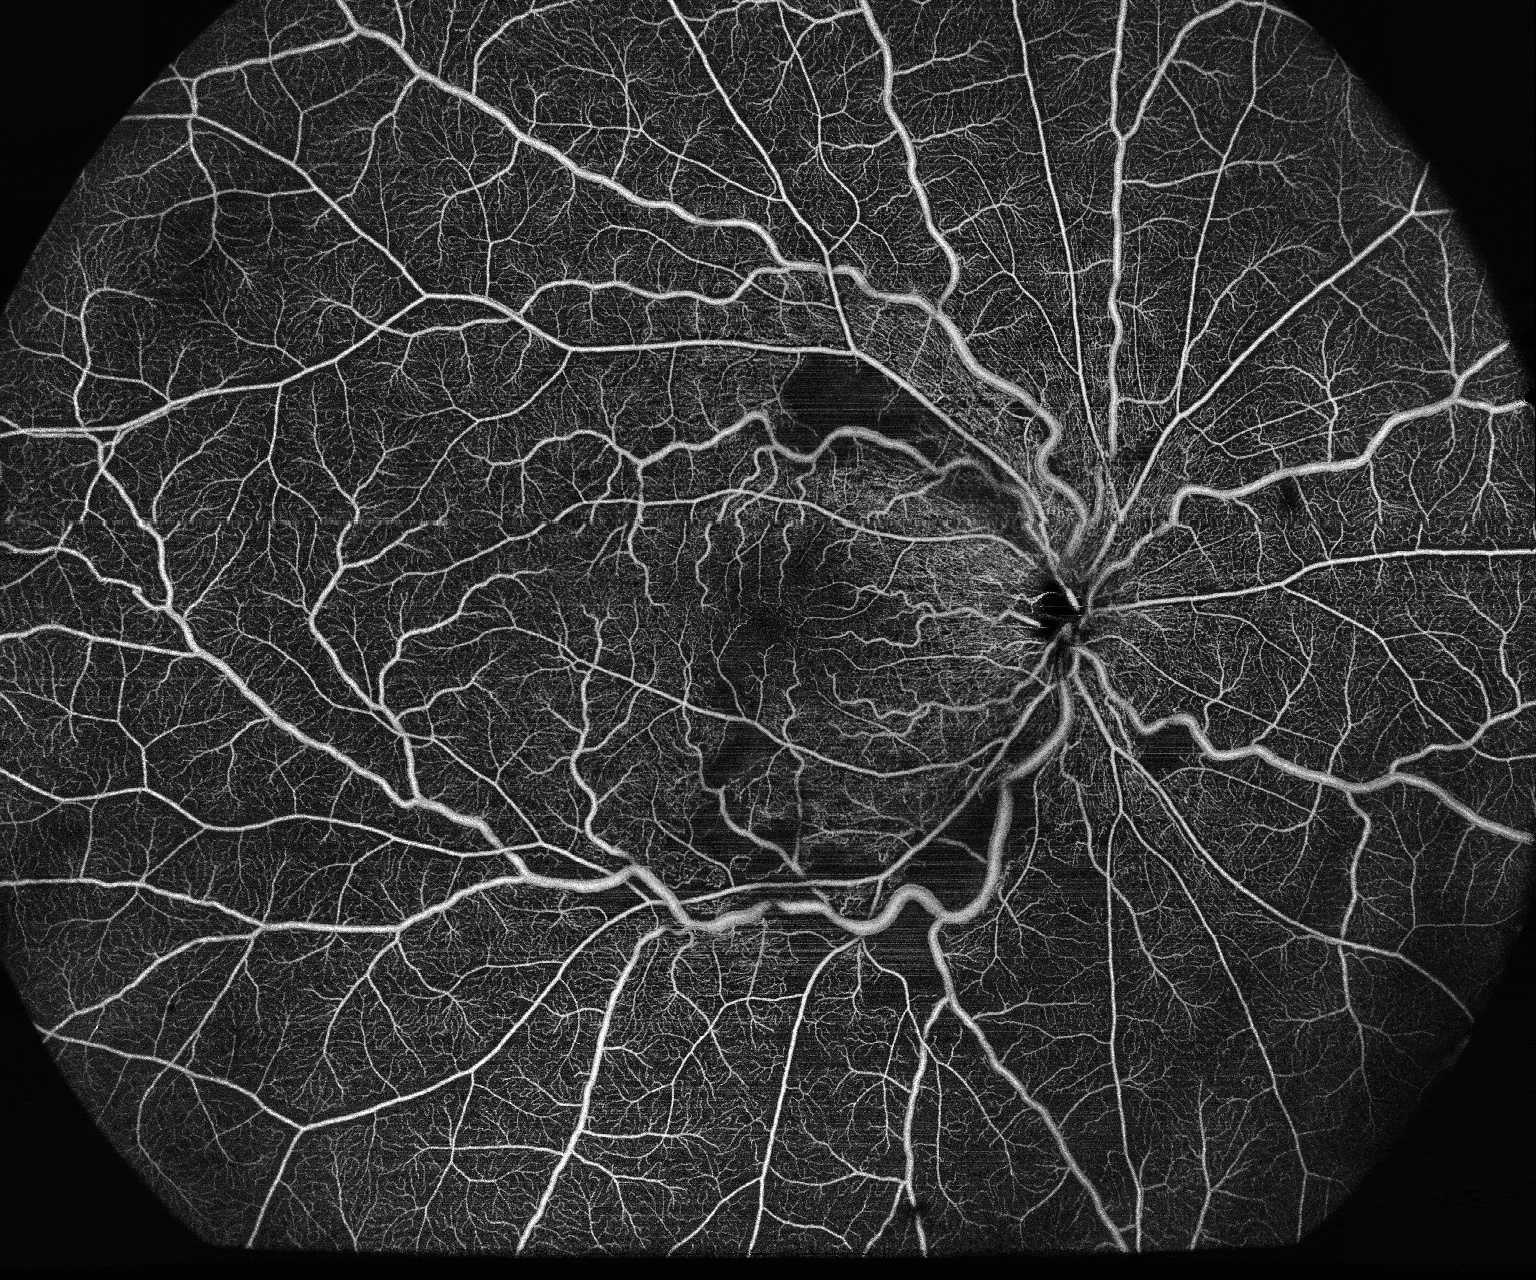

Het uitzonderlijke optische ontwerp tilt de ervaring van OCT-Angiografie naar een ongekend niveau. Dankzij haarscherpe beelden van het netvlies, de choroidea en het voorste segment, bestrijkt het systeem moeiteloos een enorm gebied in één enkele scan (tot wel 24 mm breedte OCTA in slechts 7–15 seconden).

Deze baanbrekende technologie betekent een grote stap voorwaarts voor klinische toepassingen, met name bij de diagnose en behandeling van aandoeningen zoals diabetische retinopathie (DR), veneuze en arteriële afsluitingen (RVO, RAO), en meer. Bovendien biedt de BMizar een groot aanpasbaar dioptrisch bereik, waardoor het mogelijk is om alle soorten OCT/OCTA-scans uit te voeren op kleine dieren zoals konijnen, cavia’s en zelfs muizen, zonder dat er extra lenzen nodig zijn.

Full Range OCT-A

- 3 x 3 mm, 6 x 6 mm, 12 x 12 mm, 15×15 mm, 24 x 20 in één opname

- Automatische segmentatie in 7 lagen

iSpot, voor PRP-laserbehandeling

- Unieke overlay van een retinale OCT-A met een en-face weergave die laserbehandelingspunten benadrukt

- Unieke oplossing om u te begeleiden bij uw fotocoagulatiebehandeling en -evaluatie